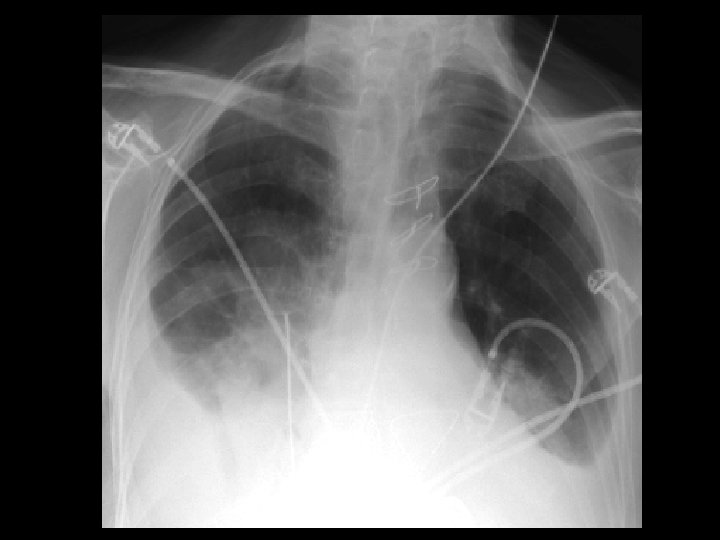

Left hydropneumothorax • Findings: – left pnuemothorax – left pleural effusion (possibly blood) • causes: – penetrating trauma – iatrogenic – bronchopleural fistula